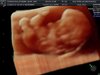

A to moje dzisiejsze zdjęcie, według usg to 9+2.chcociaz z Om wychodzi 9+6, ma 2,6cm, co według tabelki która znalazłam w internecie się zgadza z tym terminem wg OM, zapisał mnie mnie na badania prenatalne na piątek za tydzień, bo idzie na urlop, ale powiedział że najpierw sprawdzi jaka wielkość płodu i jeżeli będzie około 4,5 cm to wtedy zrobimy to badanie a jak nie to wtedy będę musiała czekać dwa tygodnie :) wracając do zdjęcia to wygląda tak jakby miał siusiaka [emoji14]